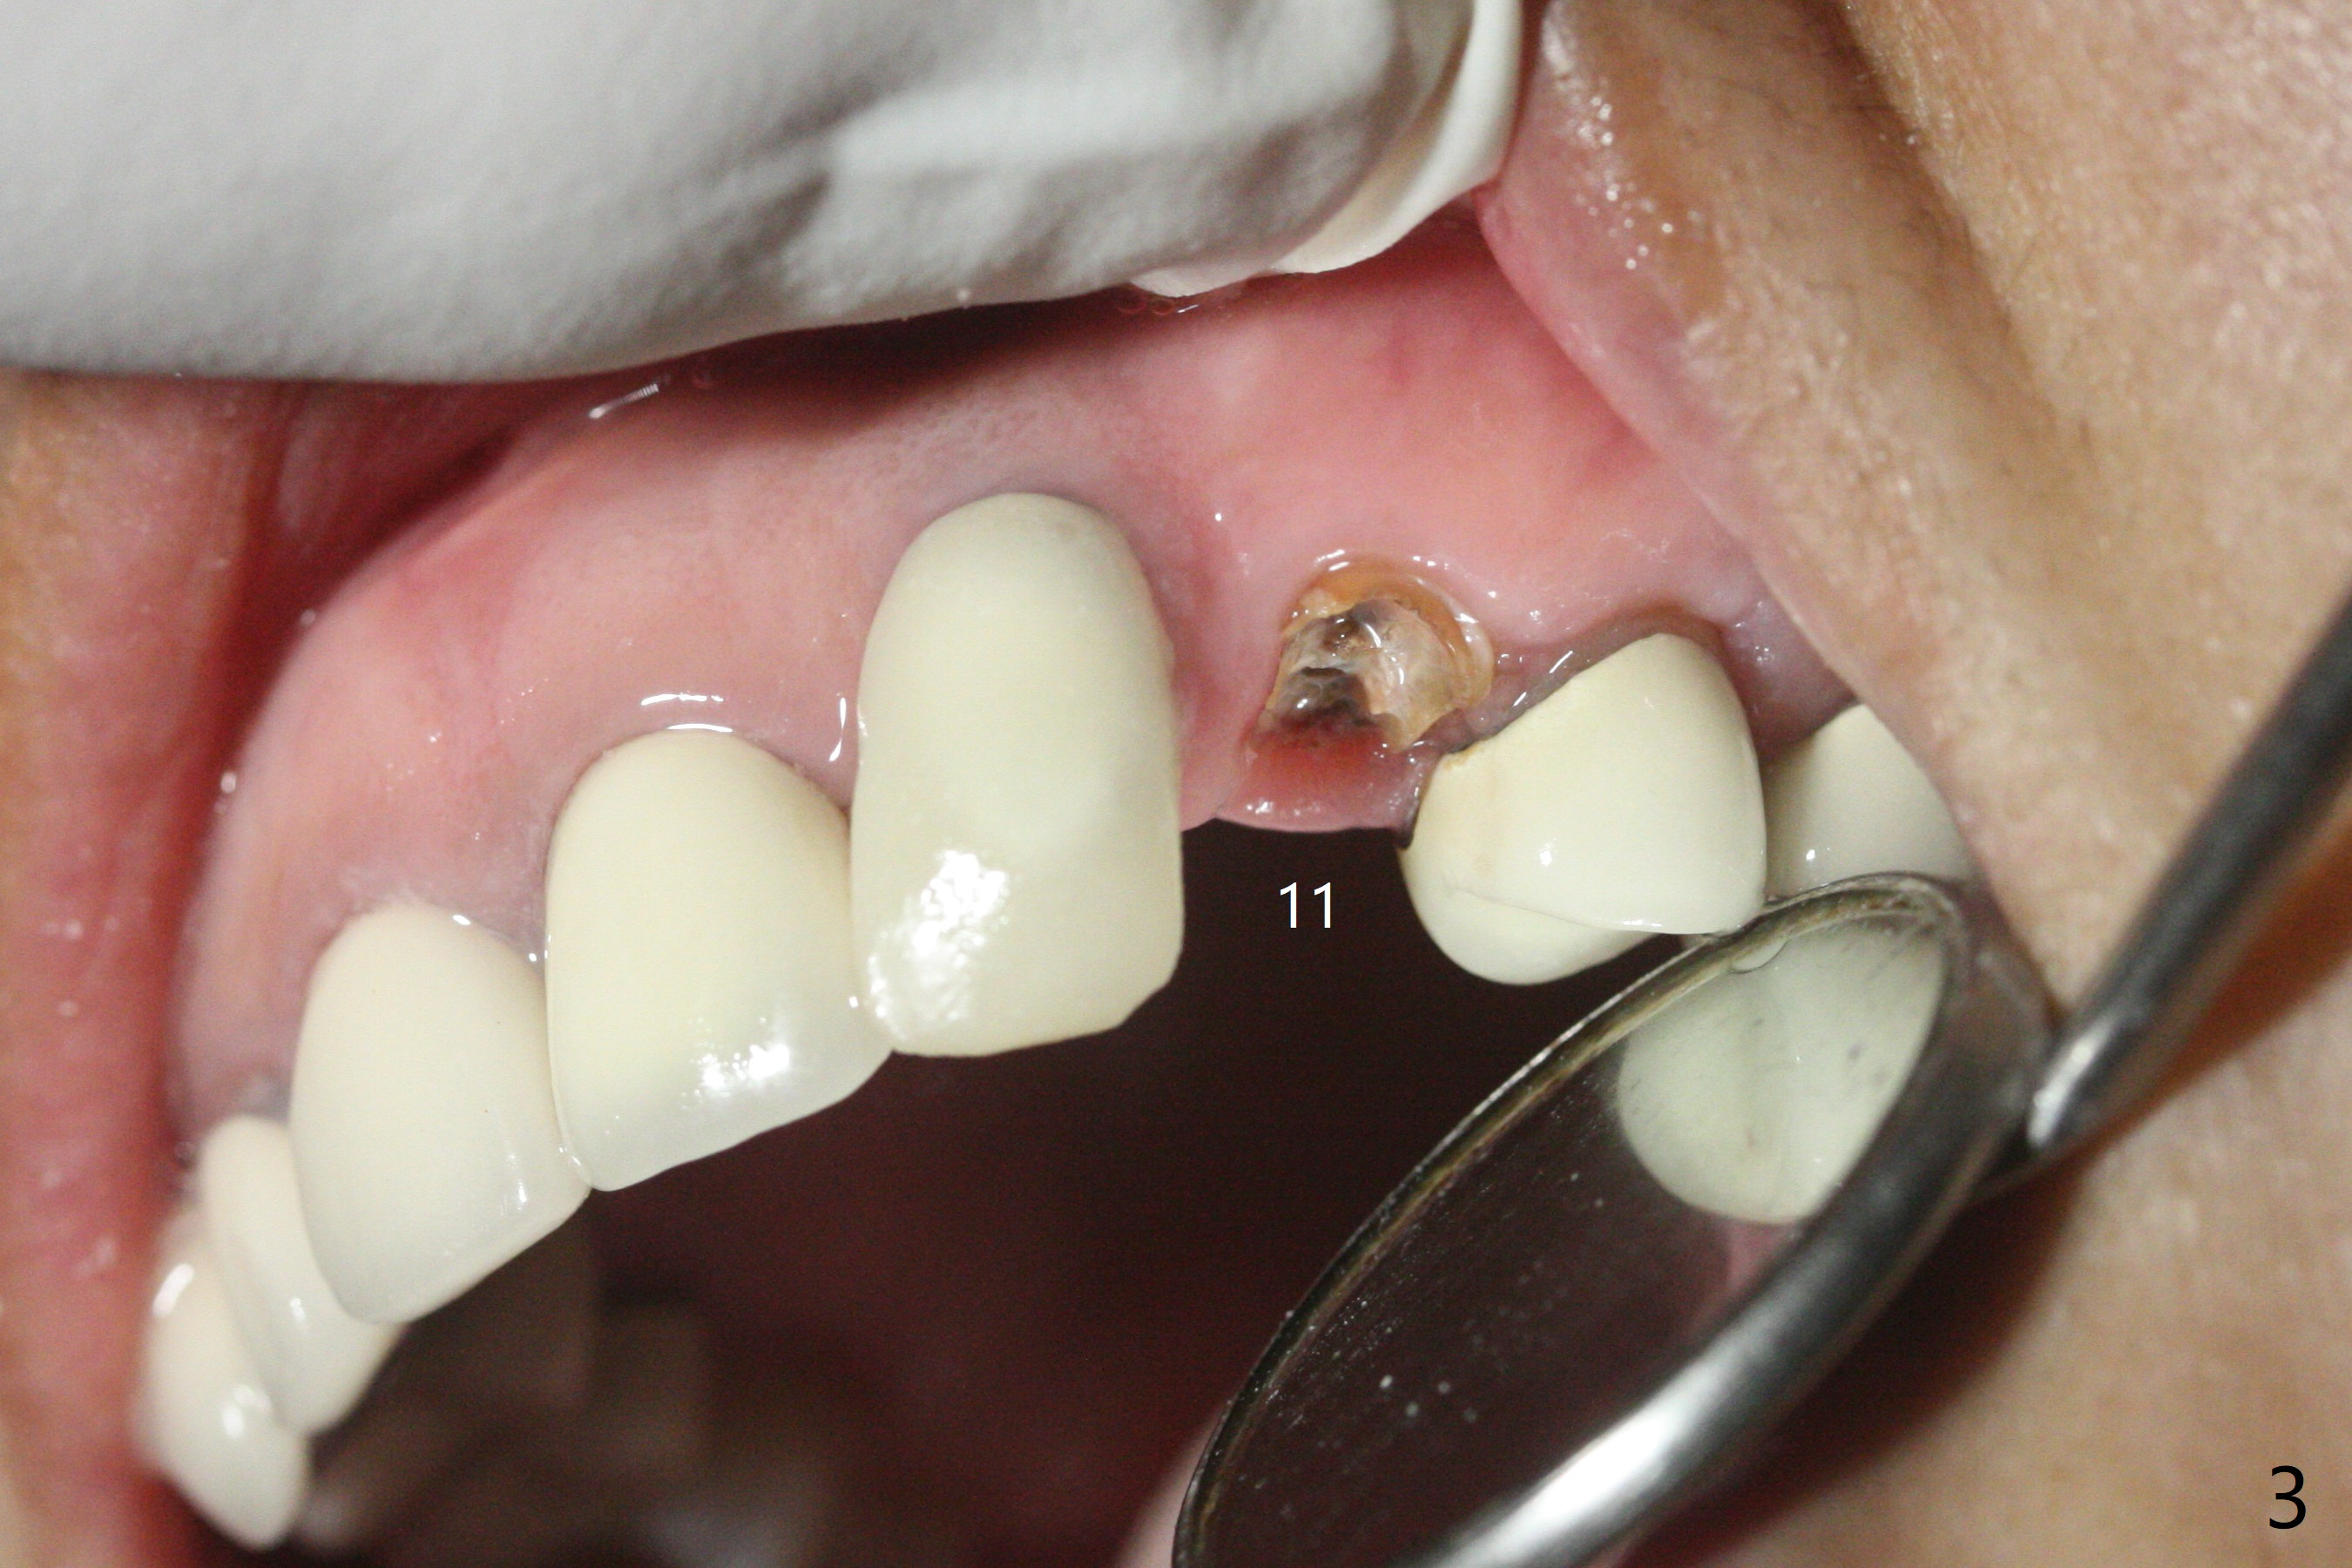

A 57-year-old woman presented to office with dislodged canine crown 10 months earlier (Fig.1). It was cemented. It dislodged again lately. She decides to have an implant and mentions looseness of the implant crown of the lateral incisor. Gingival recession is severe at #10 (Fig.2), while #11 has subgingival fracture (Fig.3). The recession is related to suboptimal angulation and buccal placement of the fixture (Fig.4), while the implant at #11 will be narrow and be placed with sufficient remaining buccal and palatal bone (Fig.5). Socket shield may be done. Prepare gingival retractors. In fact socket shield is not done because of caries in the root stump.